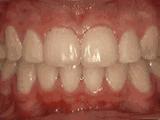

第六种:

深覆合,咬牙时,上牙盖住下牙的部位过多,影响美观,经过矫正的牙齿是这样的~